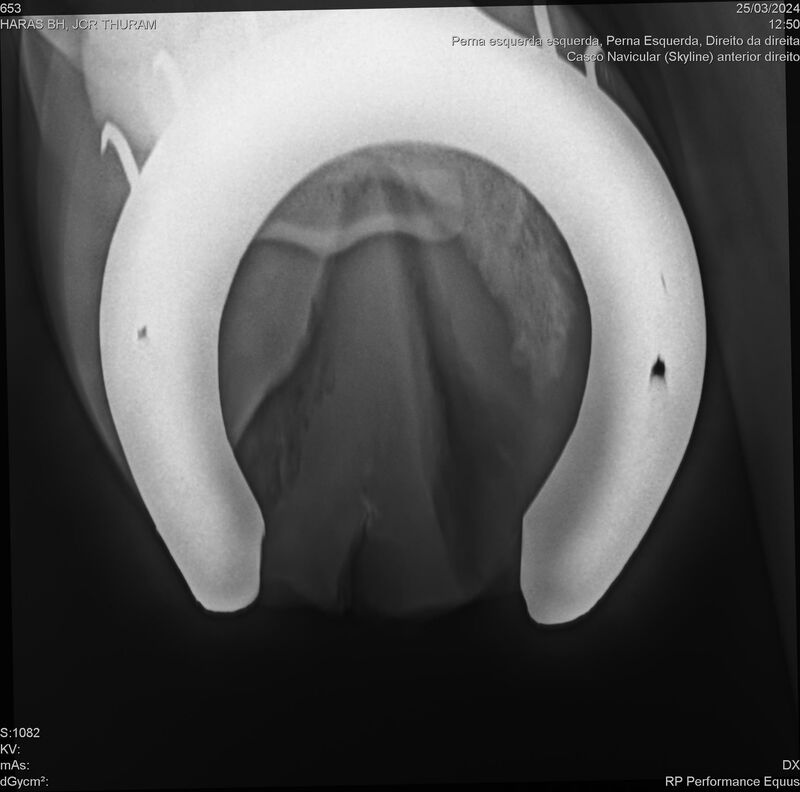

JCR THURAM

Raça: BRASILEIRO DE HIPISMO

Sexo: CASTRADO - CASTRADO

Nascimento: 10/01/2021

Altura Aproximada: 1,58

Pel.: CASTANHO

Registro: 27531-BH

Vend.: HARAS BH

Local : VINHEDO/SP